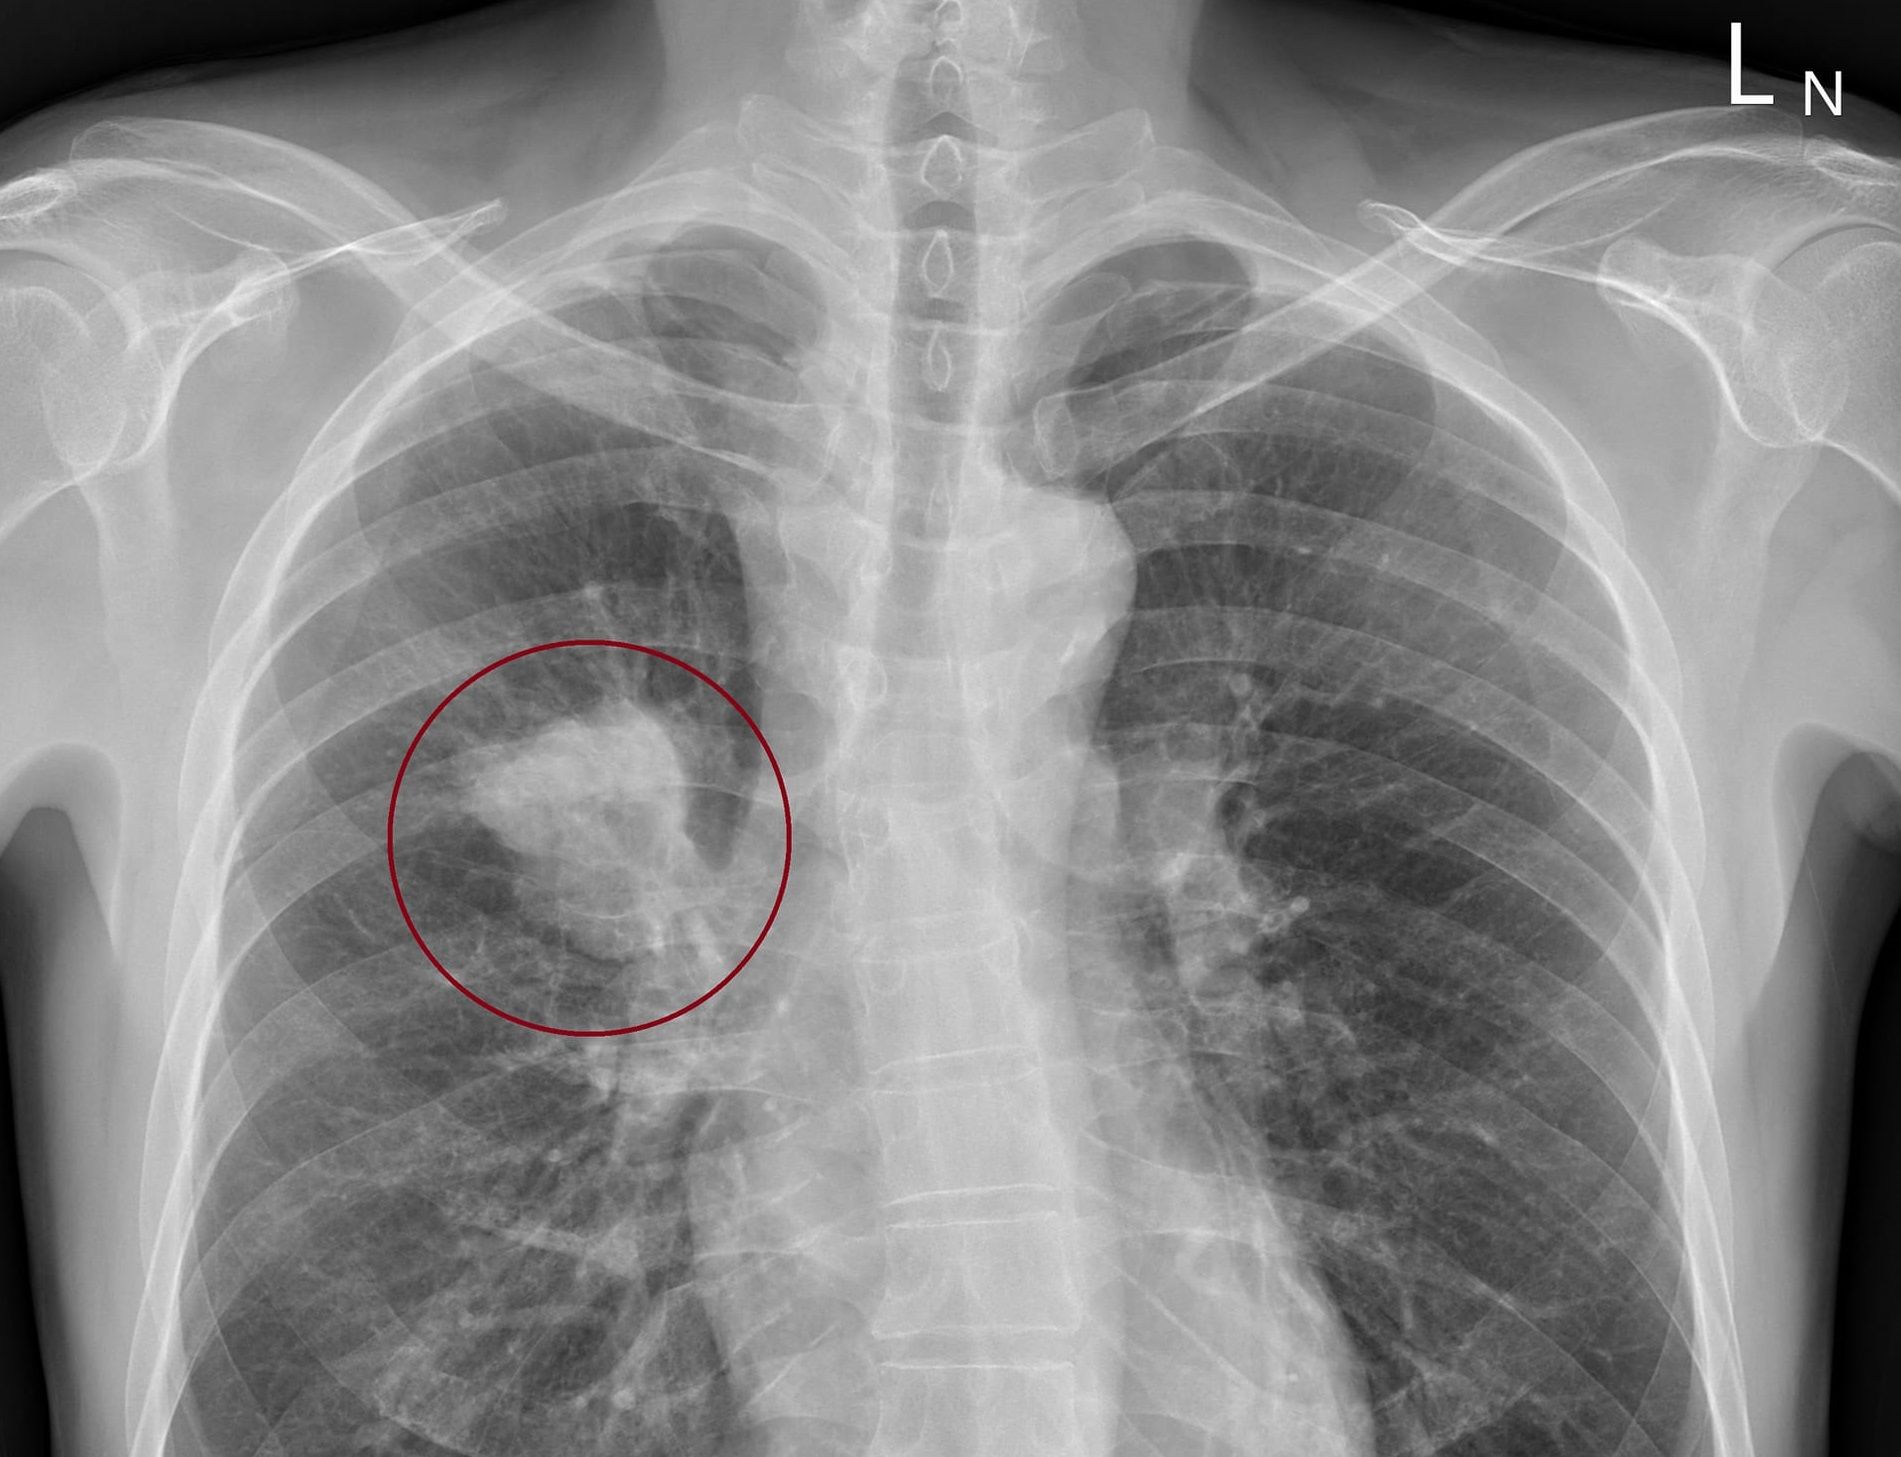

胸腔科醫師蘇一峰在臉書粉專指出,一名50歲男子在右邊脖子下面、鎖骨上面凹窩處摸到一粒硬硬的,來到門診進行檢查,他觸診時發現果然有一顆直徑約一公分的淋巴結,觸感硬硬的,但摸了並不會疼痛,讓他相當擔心,懷疑是肺部腫瘤,於是立即幫男子安排X光檢查。在X光檢查出爐後,男子當場看傻眼,因為他目前的症狀僅有一點點咳嗽,但沒想到肺部已經長了一顆五公分的腫瘤。

蘇一峰醫師說明,鎖骨上窩(supraclavicular fossa)的淋巴結,下面直通的器官就是肺部,長在肺部的腫瘤有的時候癌細胞往上面擴散時,就會轉移到這個淋巴結。由於淋巴結是身體的免疫關卡,會把淋巴管中的壞東西,包括細菌、病毒及癌細胞等等攔截下來,過去也真的遇過不少肺癌患者,在鎖骨上窩會摸到硬的淋巴結,他也提醒,如果有在該處摸到淋巴結,一定要趕快到醫院檢查。